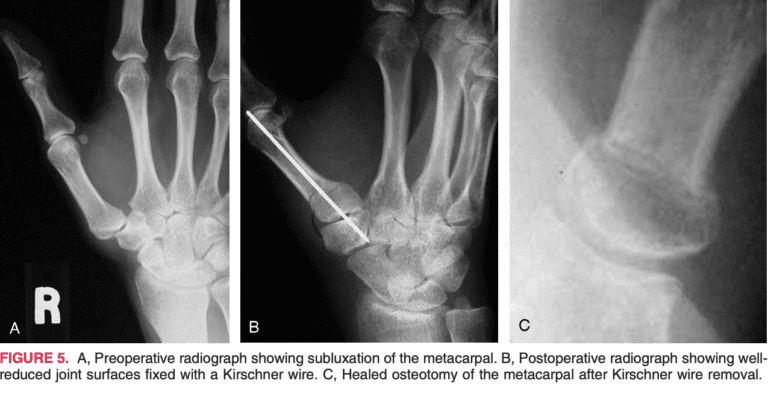

Osteoarthritis of the thumb basal joint is a common and disabling condition, and early stages of which are often seen in middle-aged women. Arthroscopic assessment of the first carpometacarpal joint allows easy identification and classification of joint pathology with mini-mal morbidity. This allows the condition to be managed either arthroscopically or converted to an open procedure as indicated. Different procedures have been described to treat different stages of this disease. The senior author has recently described an arthroscopic staging system to determine treatment for basal joint osteoarthritis. We now present our surgical technique and early clinical experience with arthroscopic synovectomy, debridement, and corrective osteotomy for arthroscopic stage II of thumb basal joint arthritis. Forty-three patients (38 women and 5 men) were arthroscopically diagnosed as having stage II basal joint osteoarthritis of the thumb between 1998 and 2001, and they were the focus of the present study. In all the patients, there was no improvement after a period of 6 to 12 weeks of conservative treatment. All the procedures were performed by the senior author. The surgical procedure included arthroscopic synovectomy, debridement, and occasional thermal capsulorraphy, followed by an extension-abduction closing wedge osteotomy in all the cases. A 0.045-in Kirschner wire provided stability to the osteotomy. By performing an osteotomy that redirects the axial loads in this joint, we have obtained satisfactory results in terms of pain relief, stability, and pinch strength. Arthroscopy allows us to not only determine the optimum indication for this osteotomy, but also to debride the joint and minimize the inflammatory response. Hence, we recommend arthroscopic synovectomy, debridement with or without a thermal capsulorraphy, and a dorsoradial closing wedge osteotomy for the treatment of arthroscopic stage II of thumb carpometacarpal joint osteoarthritis.